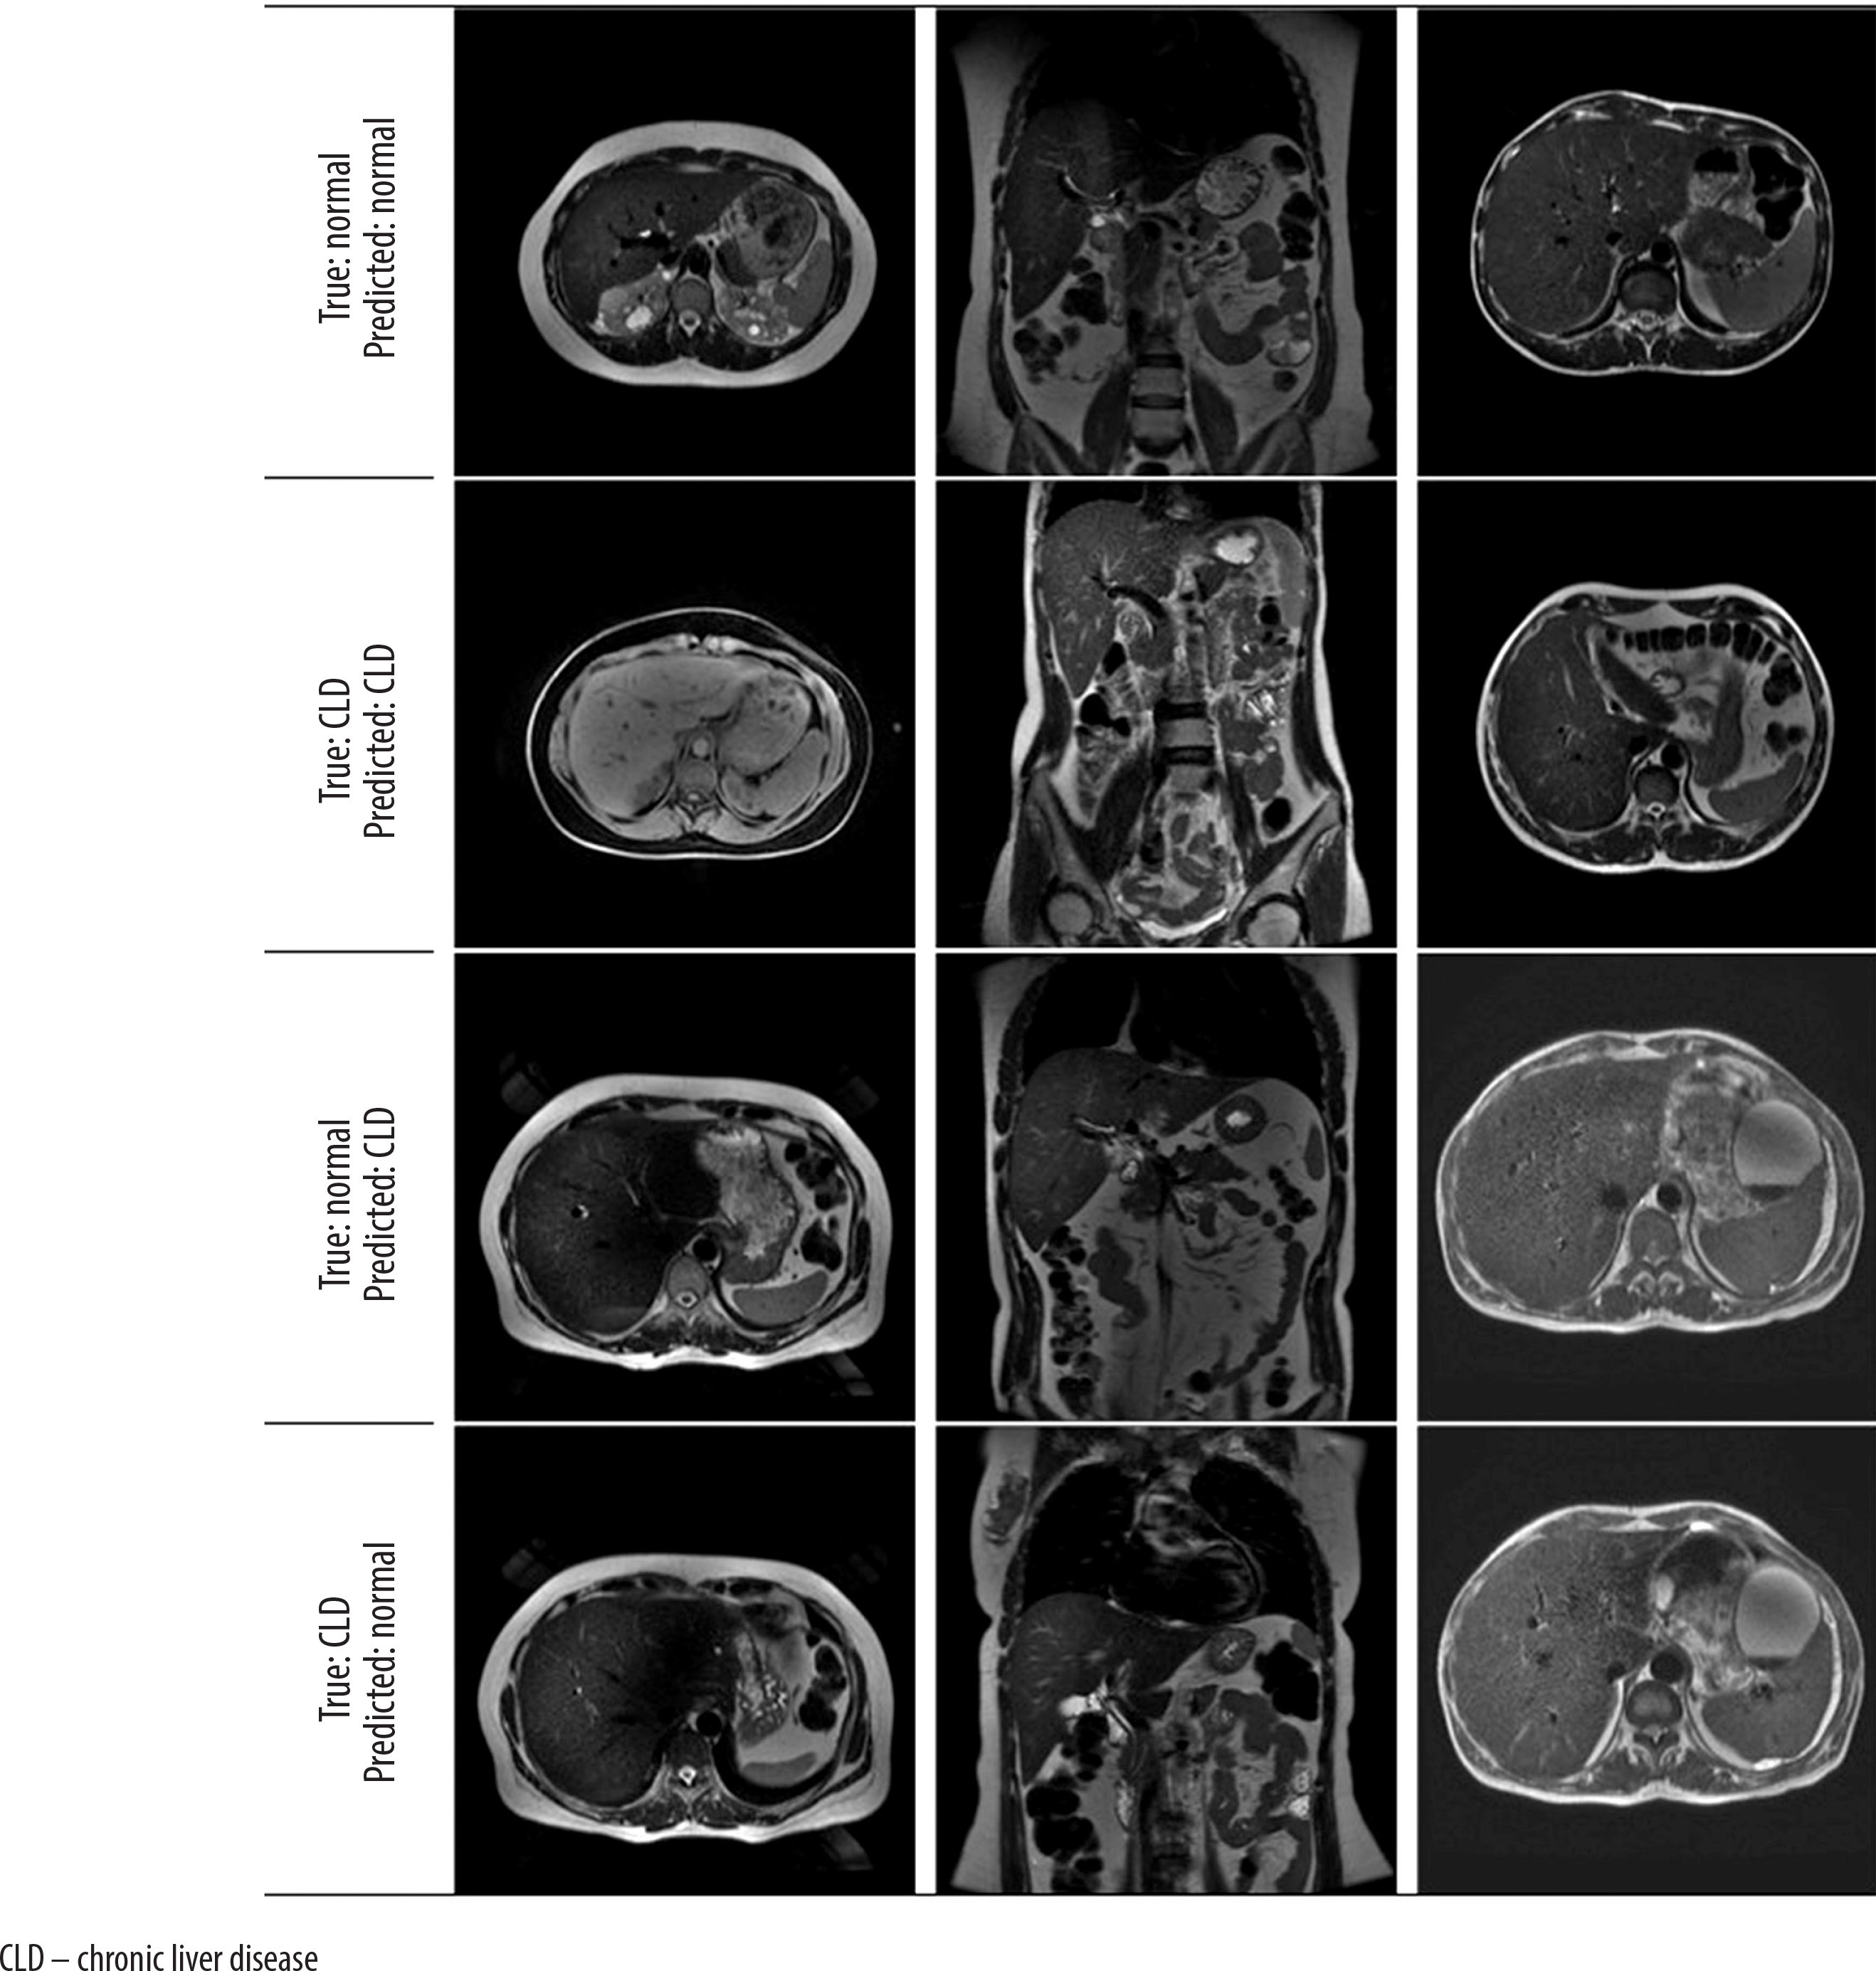

When the metrics are analyzed, according to the support criteria, there are 39 examples for class 0 (Normal) and 47 examples for class 1 (Chronic Liver). Of the model’s positive predictions for class 1 (Chronic Liver), 90.2% are considered correct, indicating a high accuracy in the model’s positive predictions. For class 1, 97.9% of the true positive samples were correctly predicted, showing that the model accurately predicted the majority of the positive class. The weighted average and macro average metrics reflect the model’s performance across both classes, and both measures show similar results, suggesting that the model provides balanced performance for both classes without bias. The model’s F1-score is 0.939, and its overall accuracy is 93%, meaning that 93% of all predictions were correctly classified (Table 1). All probabilistic outputs of the model on the test data are shown in Figure 4, and examples of patient images are provided in Figure 5.

Figure 5

Axial and coronal model test prediction outputs